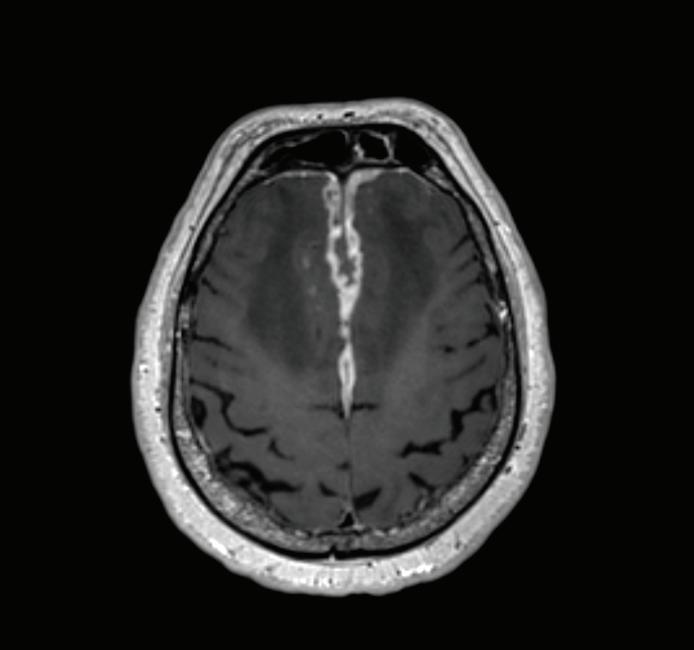

ПРЕДНА КЛИНОИДЕКТОМИЯ В. Наков

74 РЯДЪК